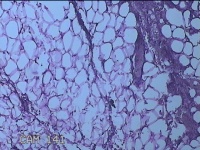

外阴部包块

性别

女

年龄

37岁

临床诊断

皮脂腺囊肿

一般病史

外阴部起包块一月余。

标本名称

大体所见

灰白暗红色包块2.3x1.8x0.8cm一个,表面糜烂,切开包块呈实性,切面灰白淡黄色,质软。

图2

有那么点像脂肪瘤。